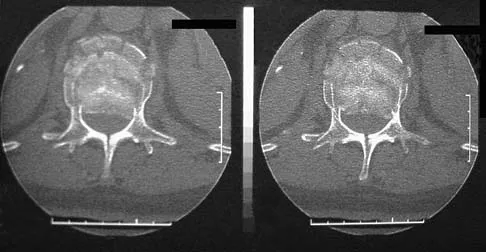

A patient who has had neck pain radiating down the arm for the past 4 weeks reports that the pain was excruciating during the first week. Management consisting of anti-inflammatory drugs and physical therapy has decreased the neck and arm symptoms from 10/10 to 3/10. He remains neurologically intact. MRI and CT scans are shown in Figures 5a and 5b. The best course of action should be

Explanation:

Although the patient has a large herniated nucleus pulposus, the pain has decreased from 10/10 to 3/10 over a 4-week period and the patient is now free of any neurologic symptoms. It is quite likely that further nonsurgical management will continue to resolve his symptoms. In the absence of any neurologic deficits, there is no evidence that the patient is at significant risk for paralysis. Saal JS, Saal JA, Yurth EF: Nonoperative management of herniated cervical intervertebral disc with radiculopathy. Spine 1996;21:1877-1883.